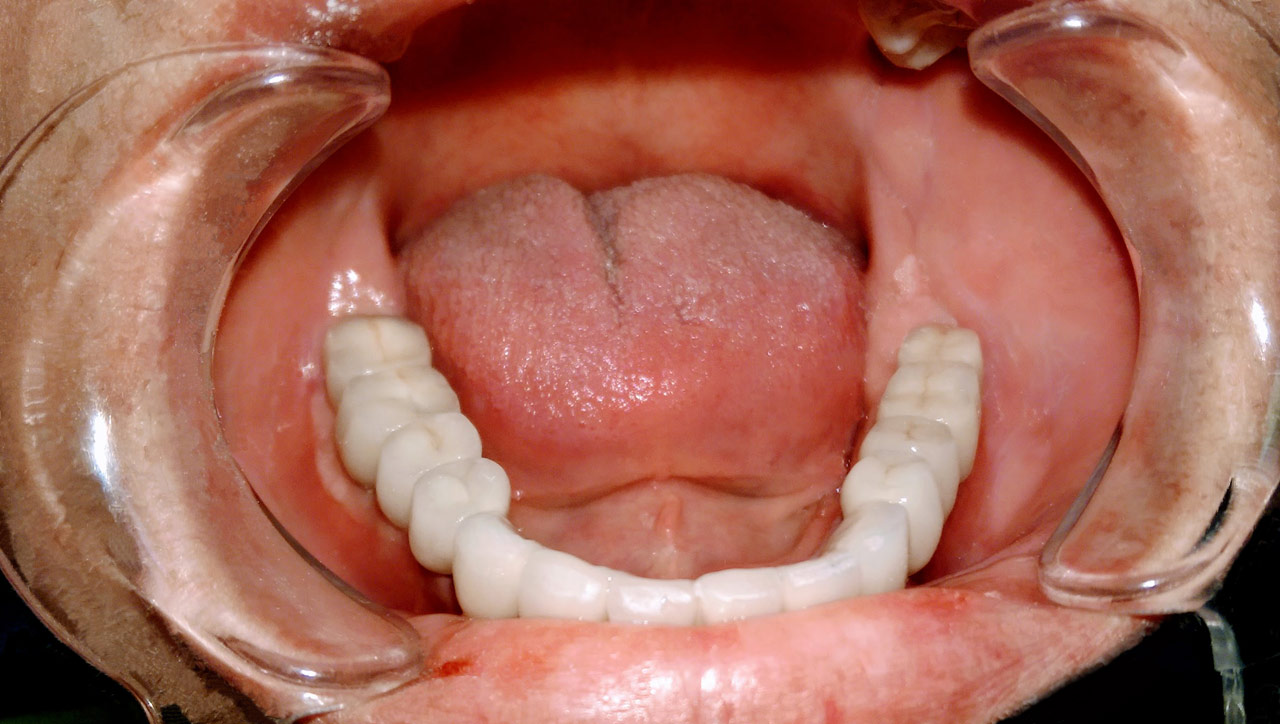

Elhanyagolt fogsor cseréje 2 nap alatt

2 nap alatt varázsoltuk ezt a szép esztétikus alsó, felső körhídat implantátumokkal megtámasztva a korábban elhanyagolt szájba. Az 1. nap 26 fogat távolítottunk el, mert annyira rossz állapotban voltak, és rögtön azonnal terhelhető IHDE svájci implantátumokat raktunk be, fentre 8, lentre 6 darabot. A sebeket összevarrtuk és intraorális szkennerrel digitális lenyomatot vettünk. 2 nap múlva pedig beragasztottuk a kész PMMA műanyag körhidakat. Dr. Kelemen Péter és a Symbion Fogtechnika munkája.